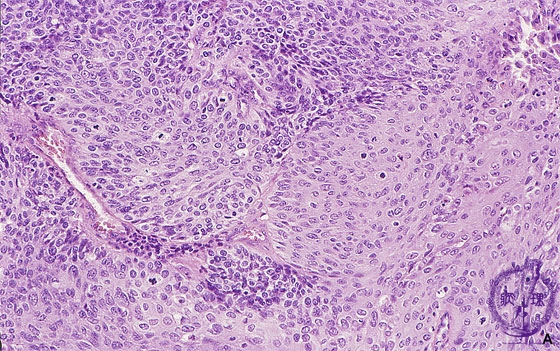

Histology (HE stain, high power): Squamous cell carcinoma of the uterine cervix. Non-keratinizing squamous cell carcinoma without keratin cancer pearls is typical of this malignancy.